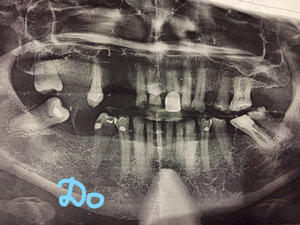

Врач поставил коронку на седьмой левый верхний зуб, несколько раз пришлось менять. В один из приемов он поставил ее на незакрытые каналы, началось воспаление. С ним очень сложно было иметь дело, я пошла к другому доктору с тем, чтобы он ее снял и почистил каналы. Со временем он их закрыл, но как выяснилось ― палатальный на 3 мм ниже и соседний ― на полтора. Есть рентген. Пожалуйста, посмотрите, можно ли ставить коронку при таком состоянии, как сейчас?

Пожалуйста, посмотрите, насколько потенциально опасно ставить коронку на зуб в таком состоянии, как сейчас. И что делать с левым виском? На фото это средний зуб, восьмерка справа от него.

6 и 7 зубы необходимо перелечить, после поставить культевые вкладки и коронки. На верхушках обоих зубов имеется обширный воспалительный процесс.